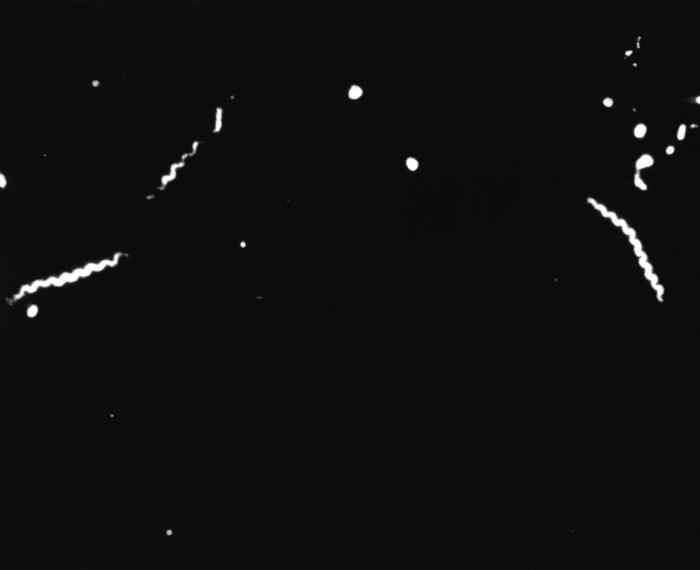

- T. pallidum organisms appear as delicate, corkscrew-shaped, rigid, uniform, tightly wound, deep spirals; coil appearance is maintained even while organisms are actively motile.

- Observe for rotational motility around longitudinal base; backward and forward movement; flexion, bending, or twisting from side to side; and snapping motion.

- Spirochetes are 6 to 14 lm long, which is slightly longer than the diameter of an erythrocyte.